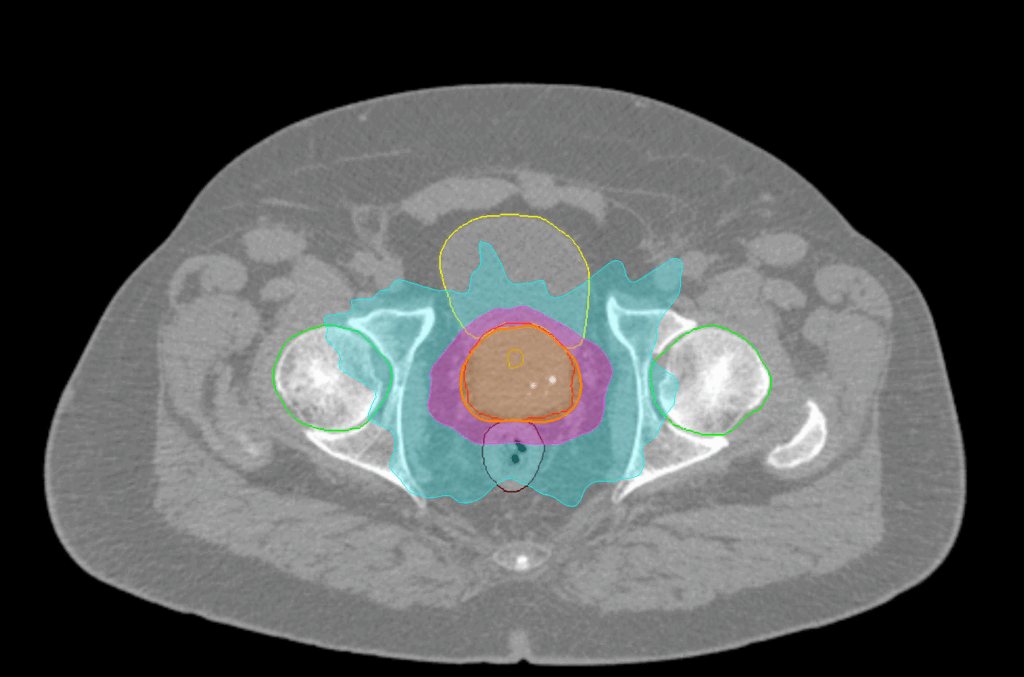

Treatment Plan Images

Dose Distributions

- Prescription to the

84% isodose line - Max. dose 43.15 Gy

New Conformality Index (nCI)

CI = 1.1 / nCi = 1.13

Gradient Index (GI)

GI = 3.34